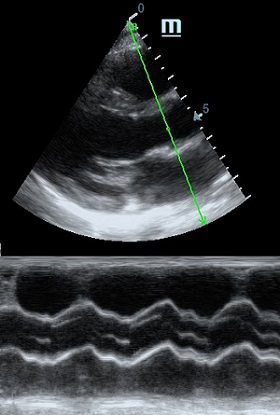

Но как же провести стандартные измерения в М-режиме, если мы его не использовали? На помощь приходит функция Free Xros M – анатомический М-режим. Имея записанную в память прибора видео петлю, мы можем провести линию М-режима в любом месте, при этом корректируя изначально не оптимальный угол.

Показатели УЗ сканирования в М-режиме

Какие показатели можно использовать при анатомическом М-режиме помимо привычных срезов через конец створок митрального клапана или синуса Вальсальве?